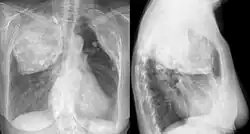

X-ray in an elderly woman after pneumonolysis | |